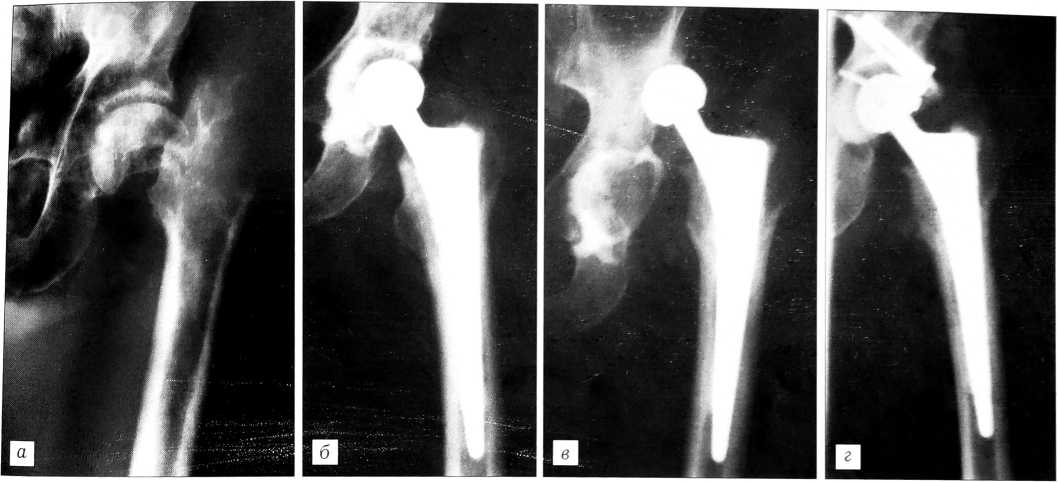

Больной П., 77 лет, госпитализирован в клинику института 5.08.96 с диагнозом: медиальный перелом шейки левой бедренной кости (рис. 1, а). Травму получил 14.07.96 в результате падения, до поступления в клинику не лечился. 8.08.96 под эндотрахеальным наркозом из переднелатерального доступа по Мюллеру произведено тотальное эндопротезирование левого тазобедренного сустава. Имплантирован протез конструкции УкрНИИТО (чашка 50 мм, ножка 11 мм, головка 32 мм «короткая»), фиксация обоих компонентов на костном цементе (рис. 1, б). Тест на вывихивание отрицательный. Рана послойно ушита наглухо. Осложнений во время операции не было. Послеоперационный период протекал также без осложнений, рана зажила первичным натяжением. Через 7 дней больной поднялся с постели, начал ходить при помощи ходунков. Для удержания ног в разведенном положении использовалась клиновидная подушка между коленями.

30.08.96 во время сна больной резко повернулся, почувствовал сильную боль в области левого тазобедренного сустава. Рентгенологически выявлен задневерхний вывих головки эндопротеза (рис. 1, в). Вправление произведено закрыто под общим обезболиванием. Наложен деротационный сапожок на 10 дней. После снятия сапожка больной занимался лечебной гимнастикой, ходил с помощью ходунков. 13.09.96 в удовлетворительном состоянии выписан на амбулаторное лечение.

29.09.96 во время сна произошел повторный вывих головки протеза. В клинике института под общим обезболиванием выполнено закрытое вправление, наложен деротационный сапожок на 2 нед.

Третий вывих возник 2.11.96, больной был вновь госпитализирован в институт. Попытка закрытого вправления не имела успеха. 28.11.96 выполнено оперативное вмешательство. При ревизии обнаружено смещение бедра вверх и кзади, бедренный компонент эндопротеза был прочно фиксирован в костномозговом канале. Отмечено вертикальное положение чашки протеза, отсутствие костной ткани заднего края ацетабулярной впадины. Чашка протеза извлечена, впадина обработана фрезами, на месте дефекта заднего края ввинчены в ряд 3 винта. Ацетабулярный компонент фиксирован на костном цементе, одновременно цементированы винты, ставшие препятствием для смещения чашки. Головка эндопротеза (прежняя) вправлена во впадину (рис. 1, г). Послеоперационный период протекал без осложнений. Вставать с постели и ходить при помощи ходунков разрешено спустя 2 нед после операции. В удовлетворительном состоянии больной выписан на амбулаторное лечение. Через 1 год состояние пациента и положение компонентов эндопротеза хорошее.

Рис. 1. Рентгенограммы больного П. а — до операции: медиальный перелом шейки левой бедренной кости; б — состояние после тотального эндопротезирования левого тазобедренного сустава протезом конструкции УкрНИИТО с фиксацией на костном цементе; в — вывих головки эндопротеза; г — состояние после ревизионного эндопротезирования левого тазобедренного сустава (фиксация ацетабулярного компонента на костном цементе с одновременным цементированием винтов, служащих препятствием для смещения чашки).

Как видим, у данного больного вывихиванию головки эндопротеза способствовали относительно вертикальное положение ацетабулярного компонента (см. рис. 1, б), а также нарушение режима сгибания и приведения конечности во время сна. Нормальная ориентация впадины эндопротеза соответствует наклону 45° относительно горизонтальной линии и 10—15° антеверсии. Более вертикальное положение впадины или изменение угла антеверсии как в одну, так и в другую сторону нарушает биомеханические соотношения в суставе, способствуя снижению стабильности в нем. С целью профилактики вывихивания головки после ее вправления необходимо наложение деротационного сапожка сроком до 2 нед для ограничения наружной ротации. Многоразовое вывихивание и закрытое вправление привели в представленном наблюдении к нарушению стабильности чашки протеза и повреждению заднего края ацетабулярной впадины.